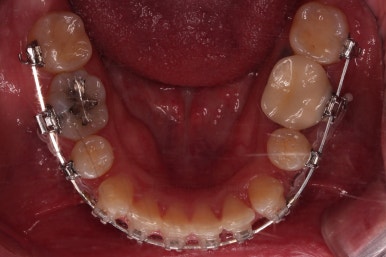

처음 장치를 부착한 사진입니다.

이번에 동래교정치과 선택한 장치는 엠파워 클리어라고 하는 자가결찰 세라믹 장치인데요.

흔히들 클리피씨라고 알고 계신 장치의 종류입니다.

엠파워와 클리피는 제조국만 미국, 일본으로 차이가 나고 큰 틀에서는 같은 장치라고 보시면 됩니다.

동래교정치과 장치 부착 사진인데요.

세라믹이라 비교적 장치가 많이 눈에 띄지 않고요.

입은 장치의 볼륨감으로 약간 튀어나오는 모습입니다.